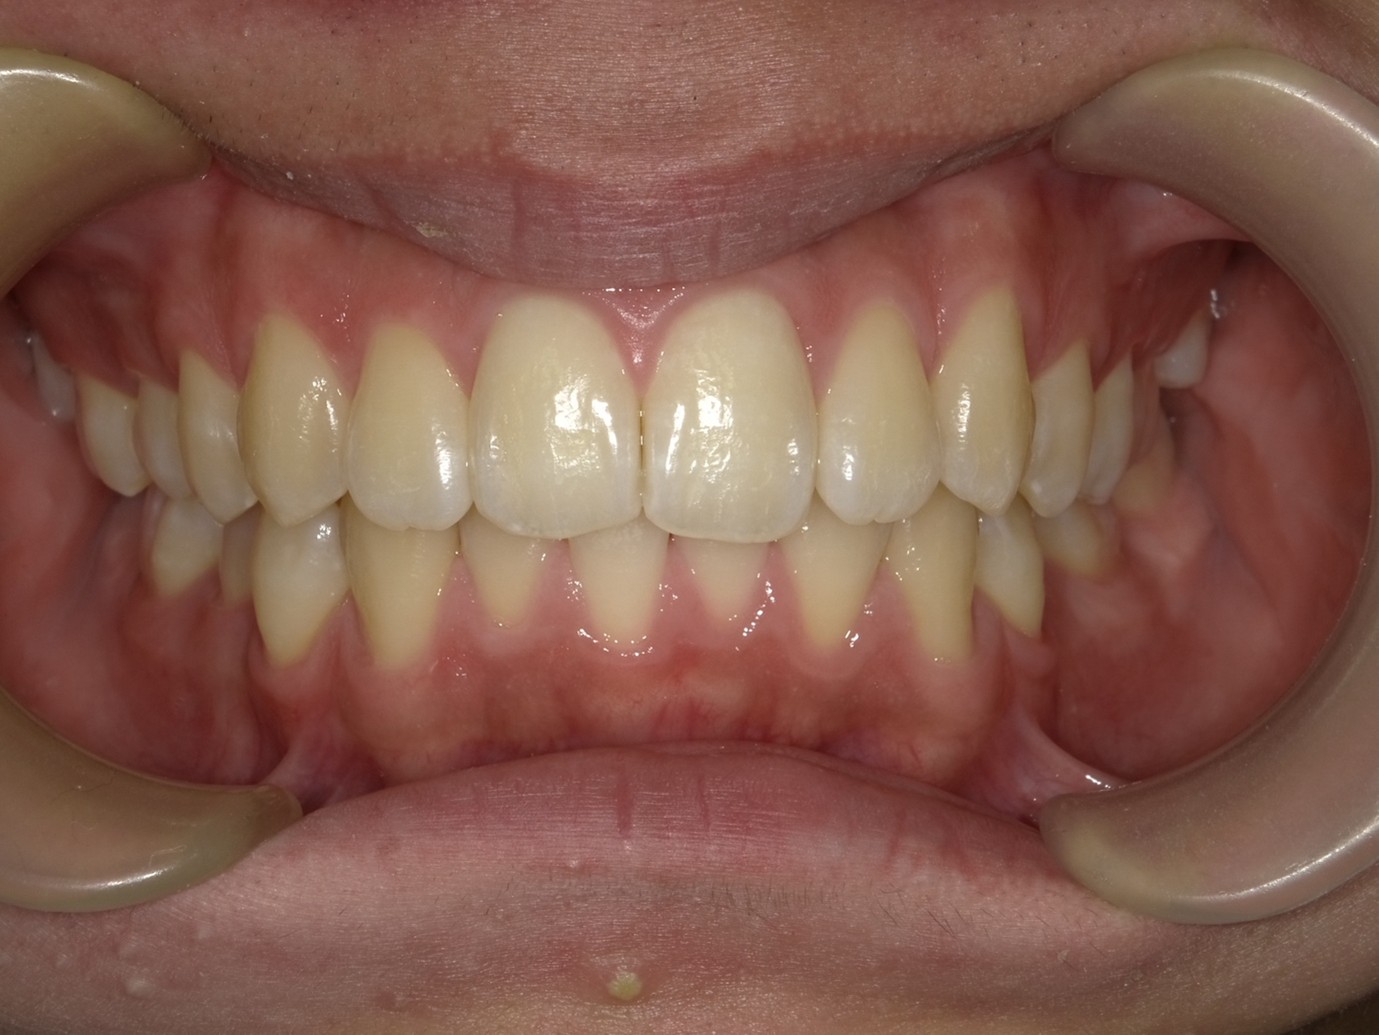

| 症例分類 | 過蓋咬合 |

|---|---|

| 主訴 | 他の歯科医院で咬み合わせを指摘された |

| 年齢 | 10歳10ヶ月 |

| 性別 | 男性 |

| 抜歯部位 | なし |

| 使用装置 | 拡大装置、咬合斜面板(取り外し式の矯正装置) |

| 治療期間 | 3年4ヶ月 |

| 保定装置 | 咬合斜面板 |

| 費用 | 相談料0円、検査料55,000円 動的矯正治療費330,000円 調整料6,600円×30回分 保定装置料0円 |

| リスク・注意点 | 上の顎の大きさに対して下の顎が小さく、過蓋咬合が生じています。これらを改善するために、幅の狭搾している歯列を側方に拡大したのち、下顎の成長を促進しました。

歯の動き方には個人差があり、予想された治療期間が延長する可能性があります。 治療中は矯正歯科装置が歯の表面に付いており、歯が磨きにくくなるため、むし歯や歯周病が生じるリスクが高まります。ハミガキを適切に行ってお口の中を常に清潔に保ち、さらに、かかりつけ歯科医に定期的に受診することが大切です。 矯正歯科装置の使用状況、定期的な通院など、矯正歯科治療には患者さんの協力が必要であり、それらが治療結果や治療期間に影響します。 治療の経過によっては当初予定していた治療計画を変更する可能性があります。保定装置の装着時間が十分確保できない場合、歯並びや、咬み合せの「後戻り」が生じる可能性があります。 上下両側第二大臼歯の萌出を観察する必要があります。(治療後の写真は成人矯正開始直前の資料です。) |